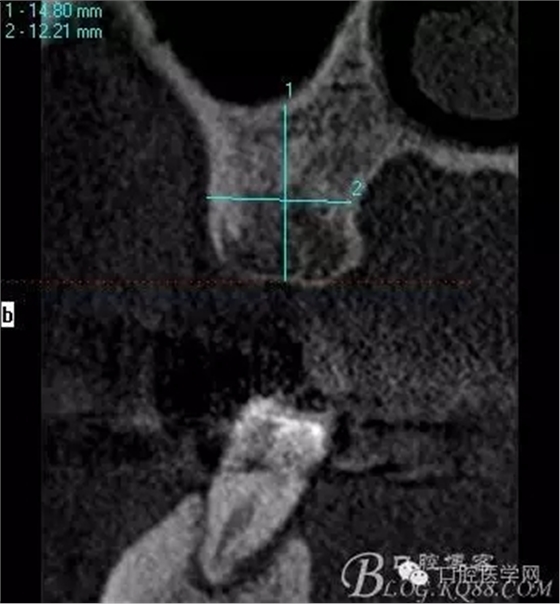

植入當(dāng)然毫無難度可言,只是想術(shù)后的方向更加賞心悅目而已,14稍微有點難度,記住 上頜牙顎側(cè)骨板肯定比頰側(cè)硬多了。 所以(特別是柱行種植體柱行鉆)永遠(yuǎn)要記住上頜牙備洞過程是會往頰側(cè)慢慢偏出去的 。(根型植體菱形鉆相對這個問題好控制點)所以我們第一鉆定位要比預(yù)計的中心點更加靠顎側(cè)多點 ,到底多多少,這個很難把握,感覺吧 。 上圖我畫了小圈的地方,是種植體離頰側(cè)和近中骨壁的距離空腔 (這個情況可以考慮植骨或者不植骨 我選擇了自體骨)。

術(shù)后片顯示方向非??梢?p style="text-align:center">

頰顎向的方向也很理想 箭頭所示 空間填滿了自體骨